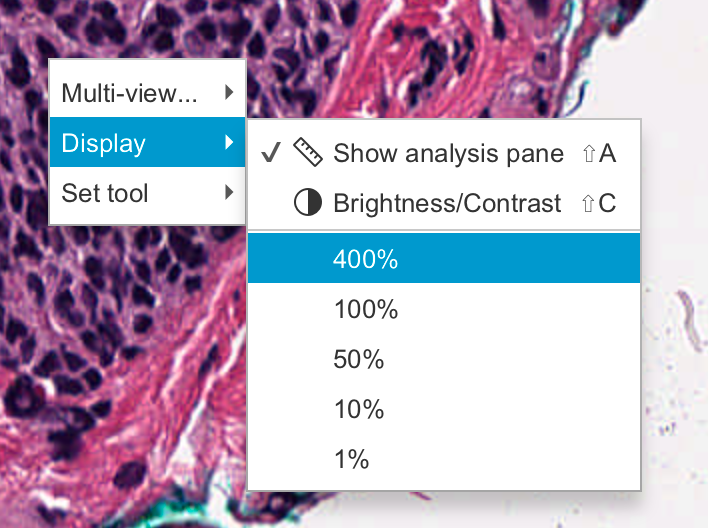

2-1:放大和缩小

要在 QuPath 中放大和缩小图像,请使用鼠标滚轮(或触控板上的等效滚动动作)。

如果您符合以下条件,也可以跳转到特定的放大倍数:

- 右键单击图像,然后选择其中一个缩放选项,例如“显示”‣“100%”,或

- 双击工具栏上的小放大倍数,然后在那里输入一个值。